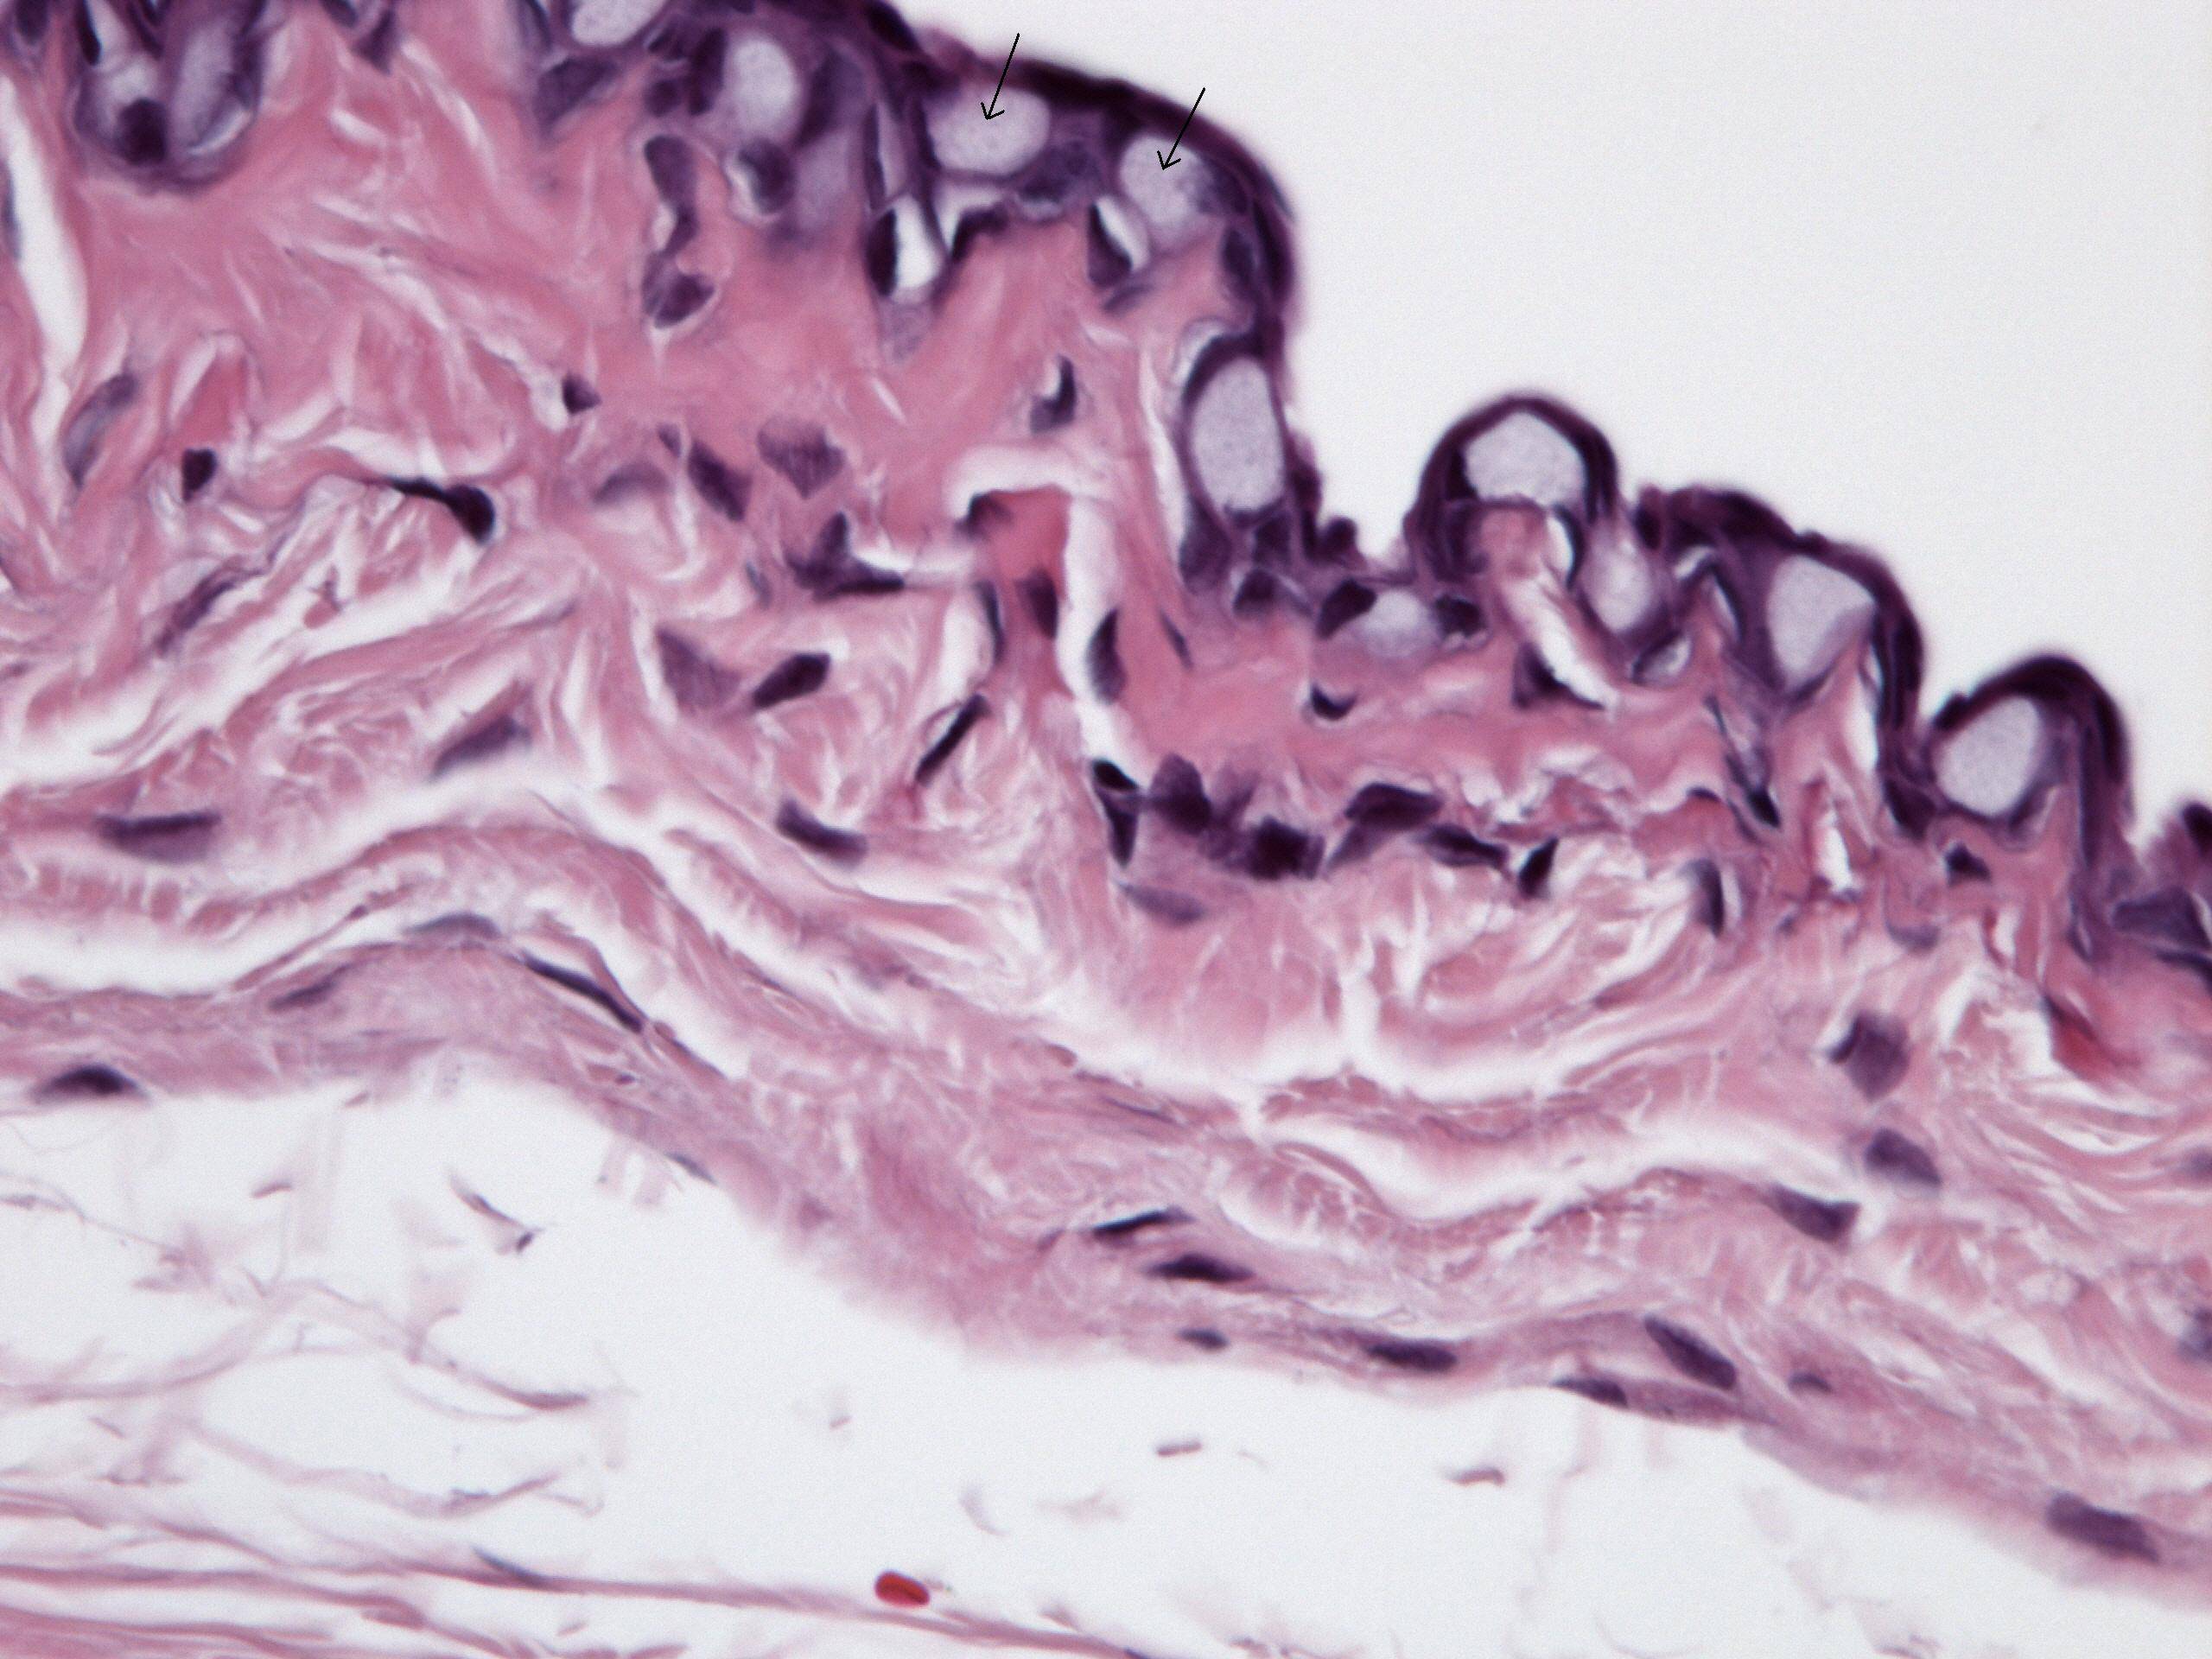

Figure 2 of SooHoo, Mol Vis 2012; 18:714-719.

Figure 2. A normal number of conjunctival goblet cells (arrows) per high power field with Hematoxylin and Eosin stain was noted in sections from the Ozurdex®-treated eyes (40× magnification).